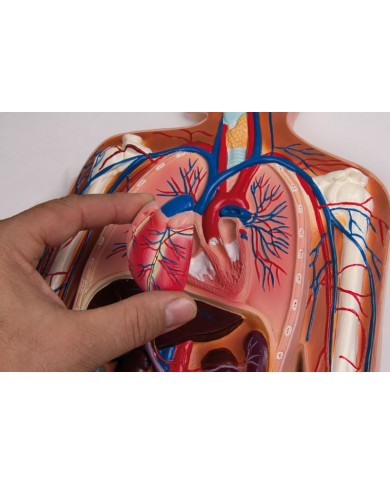

Kit composto da 3 modelli

Su Base, staccabile

Con scheda descrittiva dettagliata

Su base removibile

Su tavola, con supporto e istruzioni per l'insegnamento. Con colorante rosso e siringa di riempimento.